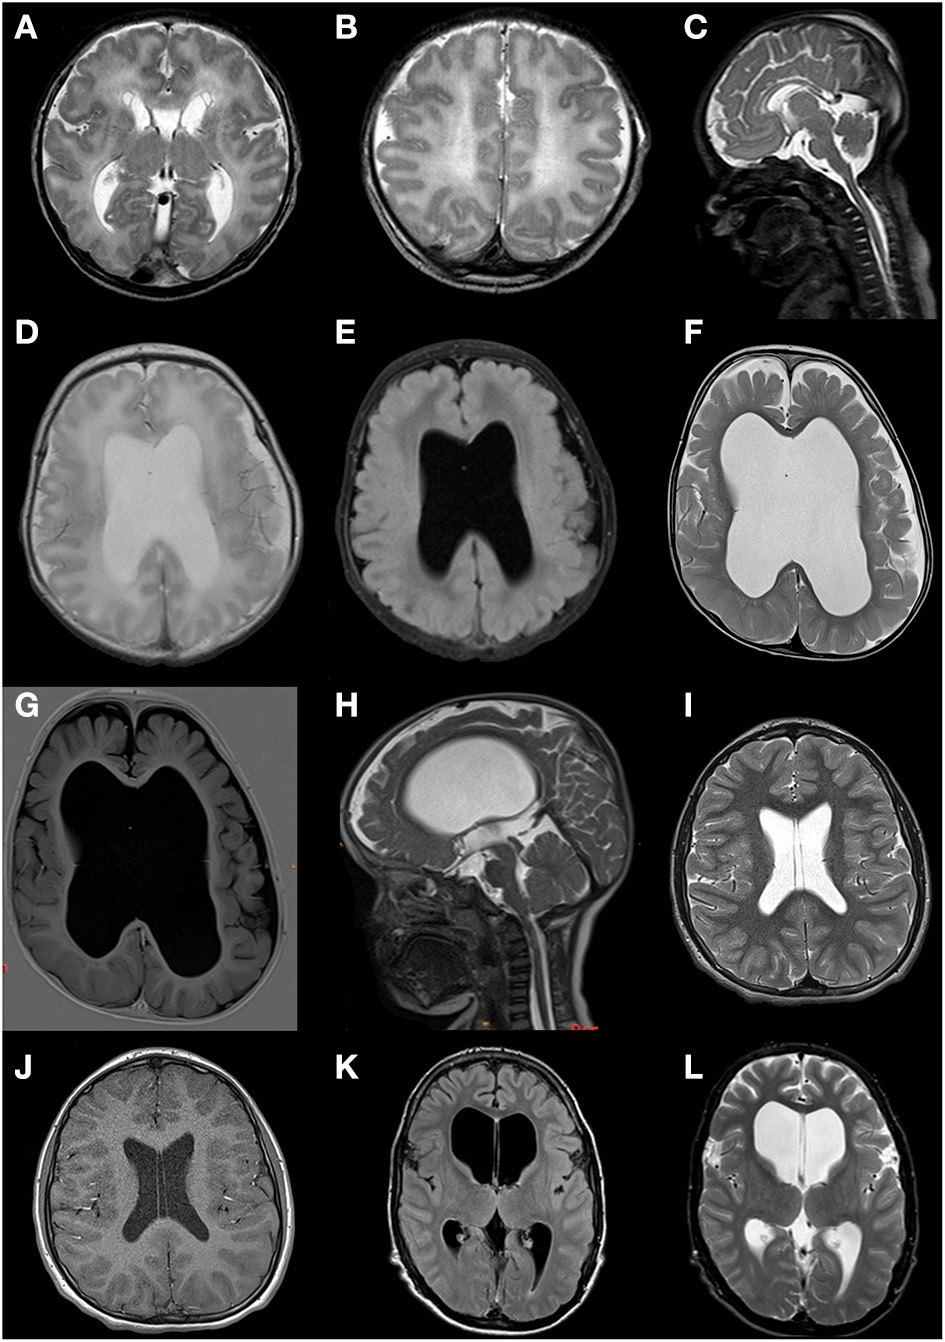

Neuroimaging

Neuroimaging was available for eight of nine patients (CT in one patient, MRI in the other patients), 75% of whom showed abnormalities as illustrated in Figure 3. Striking features present in six of eight patients (75%) included an abnormal septum pellucidum, in five of eight patients (63%) ventriculomegaly, and in five of eight patients (63%) cerebral atrophy. Further reported findings were hypoplasia of the corpus callosum and/or splenium (n = 4/8; 50%), hypoplasia/asymmetry of the cerebellum (n = 2/8; 38%), abnormal cisternae and/or sulci (n = 2/8; 25%), aqueduct stenosis (n = 2/8; 38%), abnormal basal ganglia (n = 2/8; 25%), hypoplastic brainstem (n = 1/8; 25%), abnormal periventricular white matter (n = 1/8; 13%), periventricular pseudocysts (n = 1/8; 13%), polymicrogyria (n = 1/8; 13%), cerebellar hemorrhage (n = 1/8; 13%), and a small optic chiasm (n = 1/8; 13%) (Figure 3). In patient 3, the only individual in whom sequential imaging was done, progressive enlargement of ventricles and white matter loss (Figure 3) were observed.

Figure 3

Brain MRI scans of patients 2, 3, 7, and 9. (A–C) Patient 2 at age 2 days; fetal gyral pattern with simplified sulcation, thin corpus callosum with hypoplastic splenium, widened ventricles and cisternae, subependymal pseudocysts, and a cavum septum pellucidum. (D,E) Patient 3 at age 4 days; moderate ventriculomegaly, absence of septum pellucidum, limited volume of the corpus callosum and periventricular white matter, suggestion of cortical malformation of the left temporoparietal region. (F,G) Patient 3 at age 25 months; ventriculomegaly (lateral and third ventricle) and enlarged subarachnoid space due to progressive loss of supratentorial white and gray matter volume; absence of septum pellucidum. (H) Patient 3 at age 28 months; severely enlarged lateral and third ventricle, narrow aqueduct and fourth ventricle, suggesting not only ex vacuo dilatation but dysfunction of cerebrospinal fluid. (I,J) Patient 7 at age 12 years; normal MRI but with persistent cavum septum pellucidum and vacuum vergae. (K,L) Patient 9 at age 15 years; marked ventriculomegaly (especially lateral ventricles).